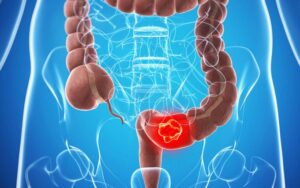

Điều trị bệnh nhân ung thư đại tràng Sigma di căn gan tại Trung tâm Y học hạt nhân và Ung bướu, Bệnh viện Bạch Mai

Điều trị bệnh nhân ung thư đại tràng Sigma di căn gan tại Trung tâm Y học hạt nhân và Ung bướu, Bệnh viện Bạch Mai GS.TS. Mai Trọng Khoa, BSCK II Nguyễn Đức Luân, PGS.TS. Phạm Cẩm Phương Trung tâm Y học hạt nhân và Ung bướu, Bệnh viện...